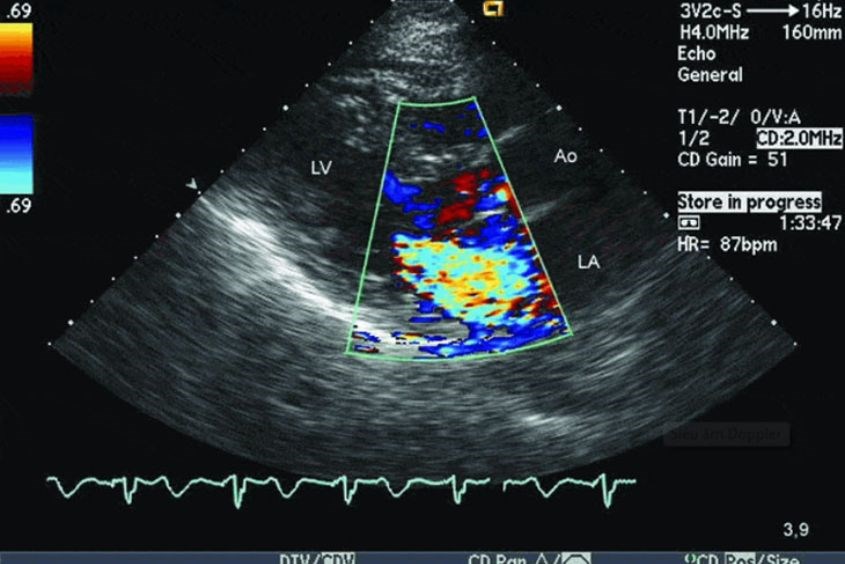

Siêu âm Doppler hay còn được gọi là siêu âm màu mô tả kỹ thuật siêu âm sử dụng sóng liên tục với mục đích để dò tìm các hướng và vận tốc của dòng chảy cơ thể. Siêu âm Doppler sử dụng sóng cao tần, loại sóng này không có trong tự nhiên, máy siêu âm sẽ tổng hợp lại các tín hiệu tần số ghi nhận được sau đó hiển thị lên màn hình với nhiều màu sắc hoặc sóng phổ khác nhau, hoặc có thể là dạng âm thanh nghe được.

Trong sản khoa, siêu âm Doppler thai sẽ đo dòng chảy chuyển động của các mạch máu, đo nhịp tim và một số chức năng khác mà siêu âm thai truyền thống không thực hiện được. Bên cạnh đó, với phương pháp siêu âm còn mang lại độ chính xác cao so với các siêu âm thông thường.

Siêu âm Doppler thai giúp phát triển dị tật tim thai